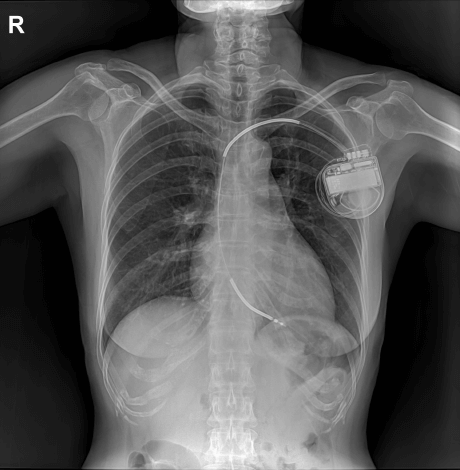

An implantable cardioverter defibrillator (ICD) is a small device implanted under the collarbone to monitor and treat life-threatening arrhythmias, helping prevent sudden cardiac death. It detects abnormal heart rhythms and can restore a normal rhythm by sending an electric shock. ICDs vary by type (single-chamber, dual-chamber, and biventricular) and may include features like data storage and remote treatment options. They are used for arrhythmias like ventricular tachycardia and fibrillation, cardiac arrest history, or when medications are ineffective. Certain patients may qualify for a subcutaneous ICD (SICD), which is placed beneath the skin in the chest, just below the armpit.